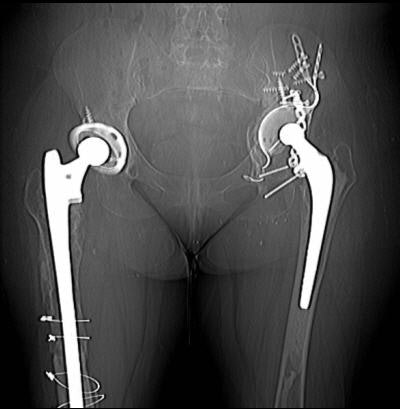

![]() |

| A 61-year-old woman with bilateral hip prostheses who was referred before surgery for evaluation of remaining "bone stock" surrounding cetabular hardware. Multislice CT was performed with thin slices (2.5-mm slice width, 1.4-mm reconstruction interval), high kilovoltage (140 kVp), and high tube current (750 mAs). Coronal reformatted image shows sparse amount of bone surrounding acetabular components (solid arrows). Wear of plastic joint liner of right hip (open arrow) is shown. Optimal scanning technique minimized metal artifacts. Buckwalter KA, Rydberg J, Kopecky KK, Crow K, Edward L, Yang EL, "Musculoskeletal Imaging with Multislice CT" (American Journal of Roentgenology, 2001; 176:979-986). |